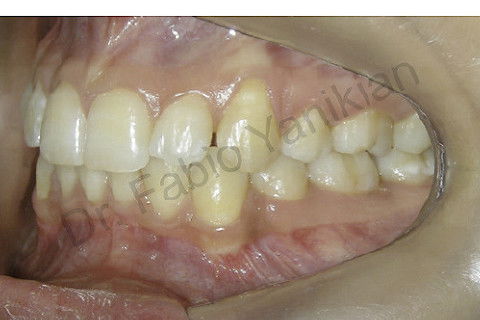

Foto lateral direita inicial

Foto lateral esquerda inicial

Paciente CL I com apinhamento superior e inferior

Evolução clínica: exo dos 4 prés, alinhamento e nivelamento, não foi necessario fazer RAS e RAI mas perda de ancoragem nos 4 quadrantes para fecar os espaços.